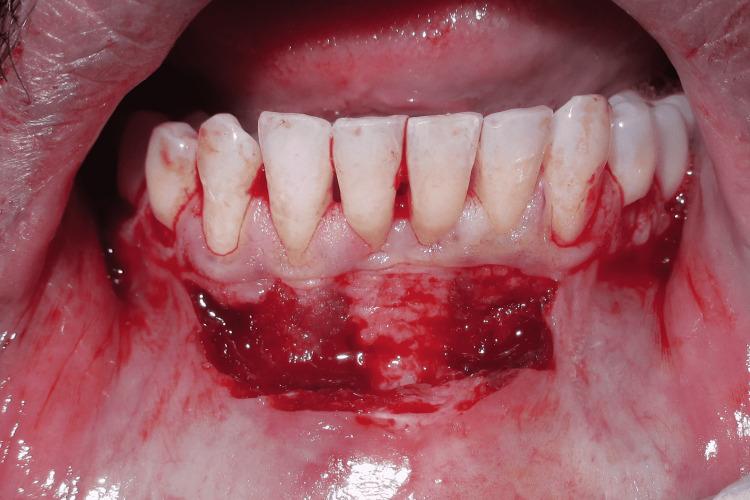

This case report describes Clark's technique of vestibuloplasty to treat shallow vestibule and, in addition, the use of free gingival autograft to augment attached gingiva to treat Miller's recession. Vestibuloplasty is performed to deepen a shallow vestibule. Different vestibuloplasty techniques are used to deepen the shallow vestibule by modifying the soft tissue attachment. A 29-year-old male presented to the Department of Periodontics and Oral Implantology, Regional Dental College, Guwahati, India with the chief complaint of bleeding from the lower anterior along with the gingival recession. Maintenance of regular oral hygiene was an added hindrance. The combined technique of vestibuloplasty and use of free gingival graft was performed to achieve dual benefits of increasing the vestibular depth and attainment of a thick gingival phenotype.

本病例报告描述了克拉克前庭成形术治疗浅前庭的技术,此外,还介绍了使用游离龈自体移植术增加附着龈以治疗米勒氏牙龈退缩的方法。前庭成形术用于加深浅前庭。通过改变软组织附着来加深浅前庭,采用了不同的前庭成形术技术。一名29岁男性因下前牙出血伴牙龈退缩,前往印度古瓦哈蒂地区牙科学院牙周病与口腔种植科就诊。保持规律的口腔卫生是一个额外的障碍。采用前庭成形术和游离龈移植术相结合的技术,以实现增加前庭深度和获得厚龈表型的双重益处。